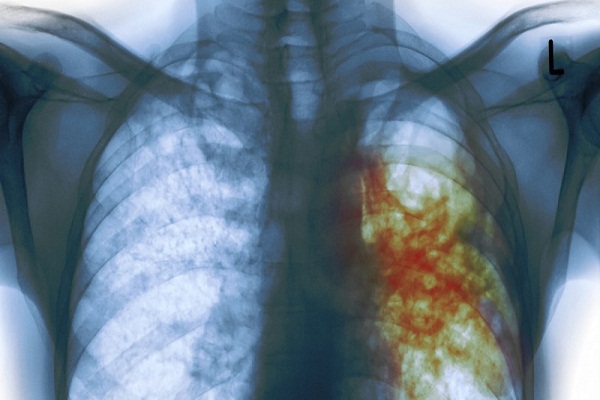

Según la OMS la tuberculosis es una enfermedad causada por Mycobacterium tuberculosis, una bacteria que casi siempre afecta a los pulmones, lo bueno es que es curable y mejor aun prevenible.

Según la OMS cuando la forma activa de la Tubeculosis se presenta, se desarrollan síntomas como tos, fiebre, sudores nocturnos, pérdida de peso, entre otros, que pueden ser leves durante muchos meses. por lo que en muchos casos el paciente tarde en buscar ayuda, ransmitiendo por desconocimiento la enfermedad.

Una vez que la enfermedad está activa, además de los sintomas antes mencionados se presenta tos, a veces con esputo que puede ser sanguinolento, dolor torácico, debilidad, y sudoración nocturna, lo que debería causar mayor alarma en el paciente infectado.